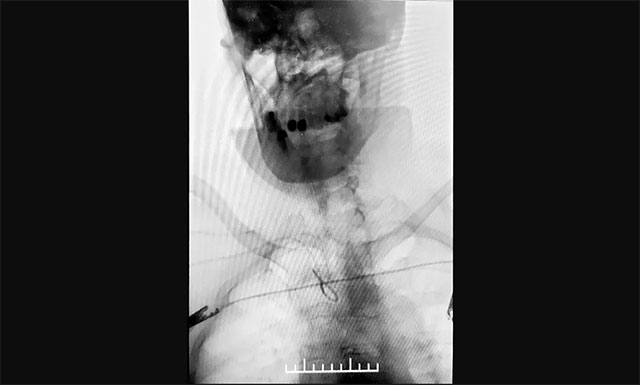

▲ 张琪博士在进行DSA手术

▲ 与传统经股动脉穿刺脑血管造影相比,经桡动脉穿刺造影相对复杂,但手术创伤小、穿刺点血肿发生率较低

考虑到患者年龄较大,不适宜长时间卧床,张琪博士遂决定经桡动脉入路行全脑血管造影术。经过详细的术前准备,2020年12月26日,张琪博士带领介入团队成功为患者进行了手术,术程顺利,耗时约30分钟,术后予桡动脉压迫器压迫术口,术后护理简单,不影响康复治疗,无术后制动,获得病人及家属的一致好评。